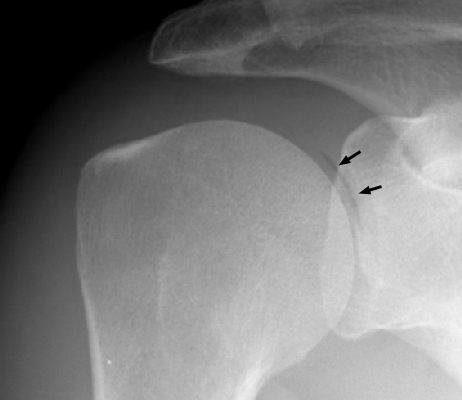

One radiograph of the shoulder (A), and one of the hip (B), both with a crescent of air-density within the joint adjacent to the head of the humerus and femur respectively. The pneumoarthrogram sign is simply the finding of gas-density within the joint and signifies that no joint effusion is present. It is a reliable sign and of great value when identified.

AP Shoulder - Click on the image for a larger versionAFrog lateral hip - Click on the image for a larger versionB